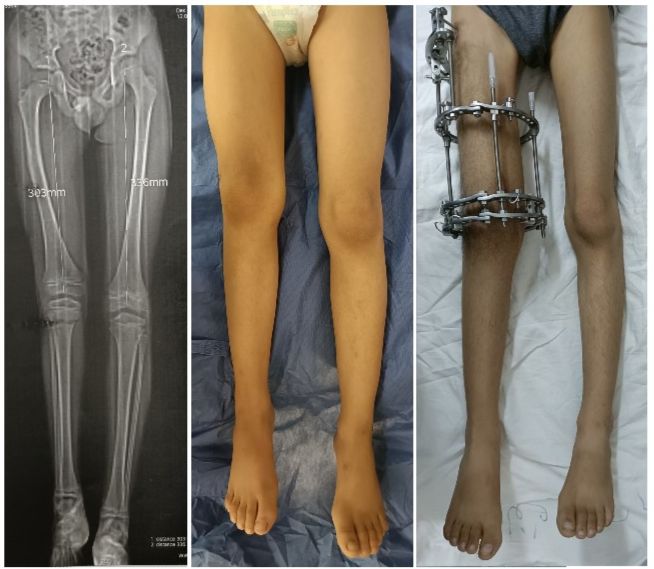

من حالاتنا